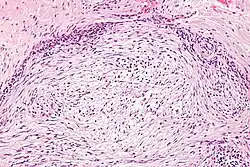

| Micrograph of nodular fasciitis showing the haphazard arrangement of cells (tissue culture-like pattern). H&E stain. | |

The microscopic histopathology of hematoxylin and eosin stained nodular fasciitis tumors consists of spindle-shaped myofibroblastic cells.[8] These cells are in a myxoid or a collagenous (high content of collagen fibers) tissue background. The neoplastic myofibroblasts are arranged in whorls and/or short bundles. These cells may show high rates of replicating as judged by their mitotic index, but these mitoses are normal in appearance. The tumor tissues often contain red blood cells, lymphocytes, and giant osteoclast-like cells, and may contain sites of bone-like tissue.[10] NF is sometimes classified into three subtypes based on its predominant histopathological pattern: myxoid or reactive (type I), cellular (type II), and fibrous (type III).[4] These patterns appear related to the duration of the lesion, with the myxoid variant tending to have the shortest duration and the cellular and fibrous variants tending to have progressively longer durations.[14] Immunohistochemical analyses indicate that the cells in NF usually express smooth muscle actin, muscle specific actin, and vimentin proteins but generally do not express CD34, S-100 protein, desmin, trypsin, factor VIII, F4/80, or HLA-DR1 proteins.[10] Uncommonly, the cells in NF tumors express the CD68 (a histiocyte-specific marker) protein.[4]